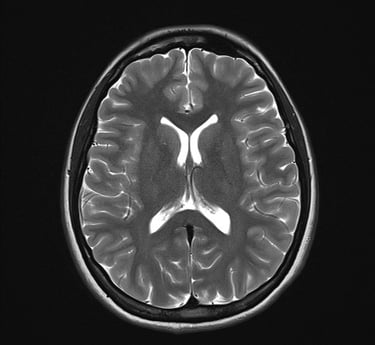

Serviço de segunda opinião e revisão técnica de exames de imagem em Neurorradiologia e Cabeça e Pescoço, com análise criteriosa de Tomografia Computadorizada (TC) e Ressonância Magnética (RM), fundamentada em critérios radiológicos atualizados e correlação clínico-radiológica.